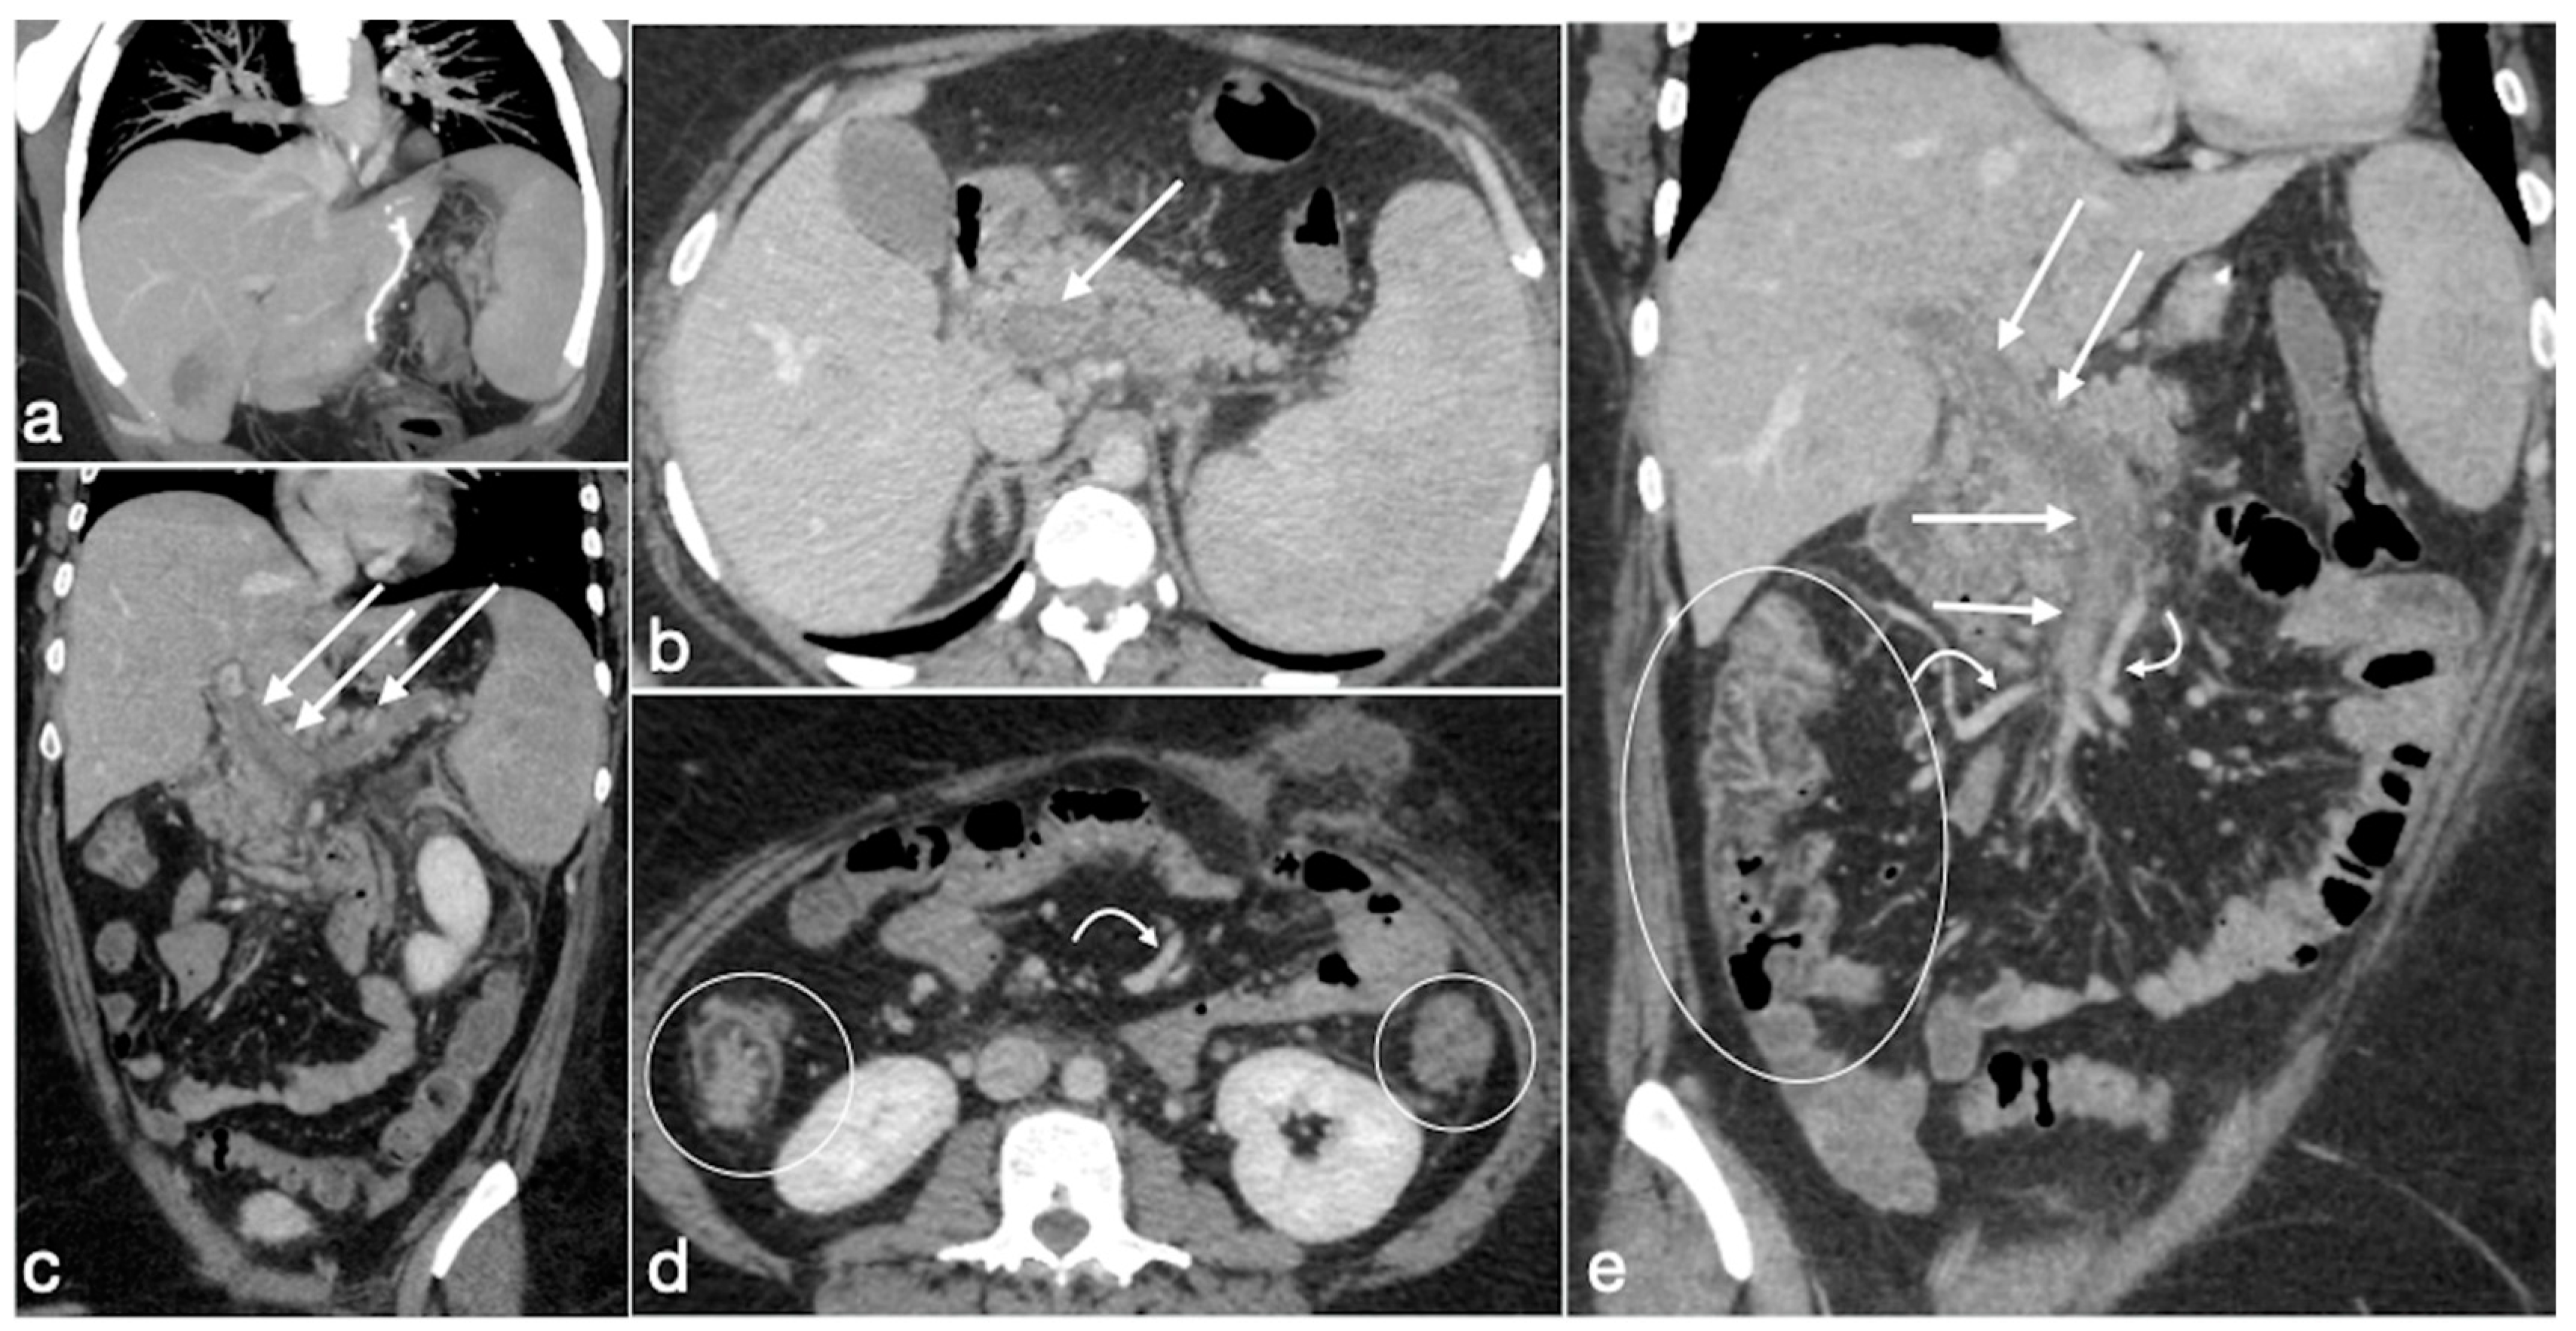

3.3.5. OAGB-MGB

- Marginal ulcers

- Internal hernia

- Anastomotic stenosis